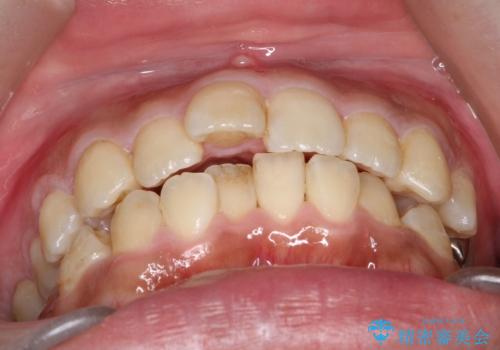

- 主訴:学生時代に矯正治療したが、後戻りしてしまった。上下前がのガタつきを治したい。

ワイヤー矯正(審美装置)非抜歯 治療期間:1年8か月

途中、大臼歯の遠心移動のためリンガルアーチを使用しています。